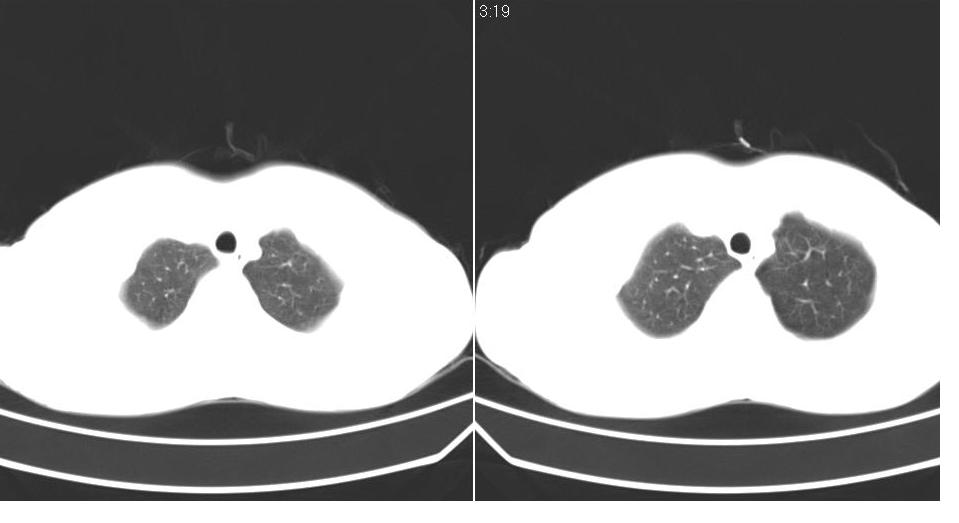

男 21岁,胸闷。

右侧包裹性积液(结核性可能大)。

右侧胸腔积液,部分呈垂滴状,包裹了,最常见的原因是结核引起的